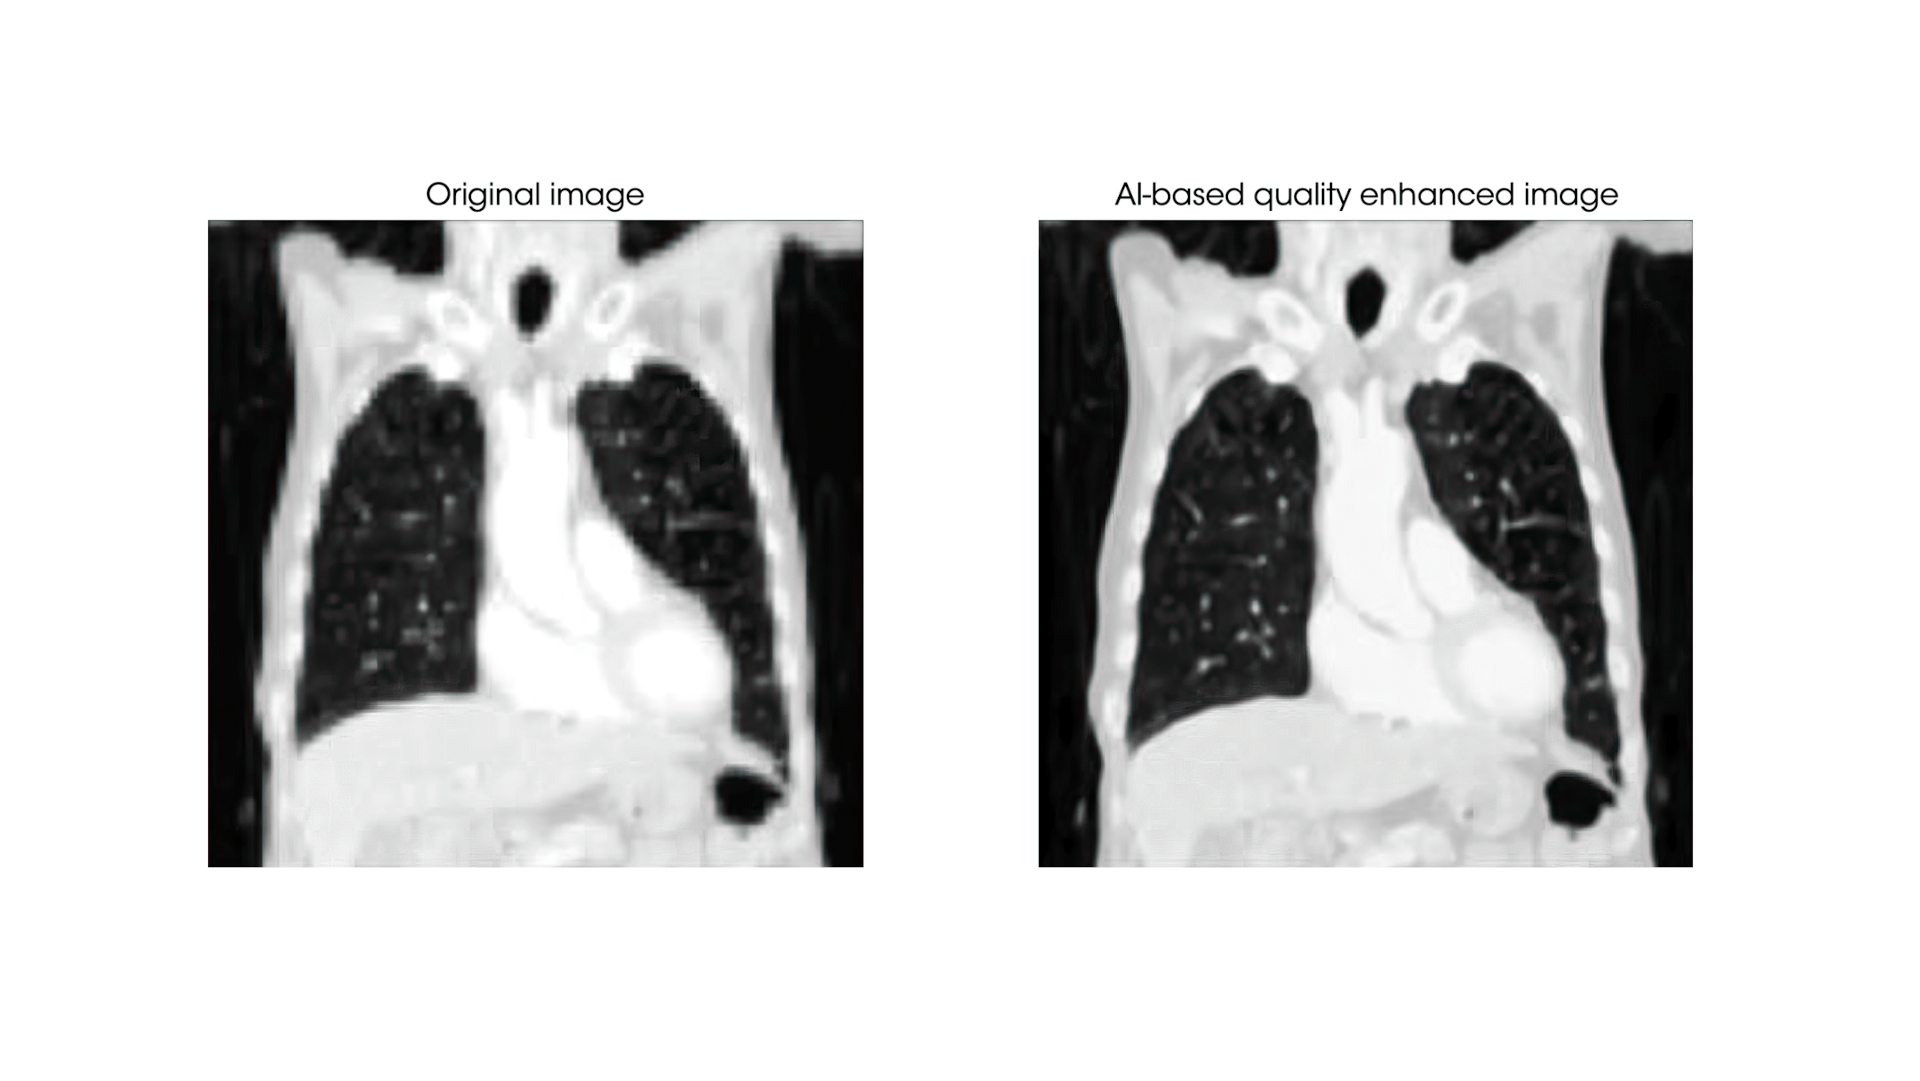

- Quality enhancement algorithms: These algorithms significantly improve image quality by reducing artifacts, enhancing resolution, and augmenting the contrast between anatomical structures. This provides radiologists with clearer, more precise images for reporting.